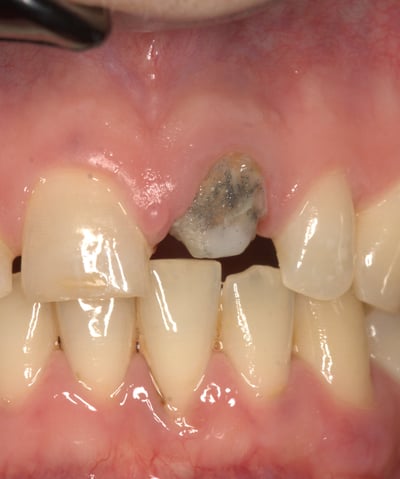

Trattamento endodontico inadeguato: il precedente trattamento canalare era insufficiente, lasciando il dente vulnerabile a infezioni e compromettendone la prognosi a lungo termine.

Perno moncone inadeguato: la mancanza di stabilità del perno esistente causava la continua decementazione della corona, rendendo necessario un intervento risolutivo.

Moncone non ritentivo

Trattamento Canalare Incongruo

2. Sostituzione del Perno Moncone

Il perno moncone preesistente è stato rimosso e sostituito con un perno in fibra di vetro. Questo materiale offre vantaggi significativi: